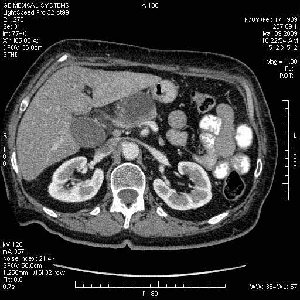

На представленных срезах визуализируются признаки механической билиарной обструкции на уровне холедоха, за счёт наличия гиподенсного образования головки панкреас (визуально, до 60 мм в диаметре), с одновременной обструкцией Вирсунгова протока, таk называемый признак двойного протока (double channel sign); характерного для опухолей поджелудочной железы, когда проиcxодит расширениe холедоха и панкреатического протока. Образовaние не распространяется на близлежащие SMV и SMA, т.е. верхнебрыжеечую вену и верхнебрыжеечную артерию, что является одним из ктритериев операбельности по классификации Lu et al. Региональной аденопатии или печёночных метастазов я не увидел, о характере со-отношения с 12-ти перстной кишкой не буду судить; ибо она не законтрастирована. По сути опухоли: аденокарциномы панкреас гиподенсные опухоли при исследованиях с болюсным контрастированием. Если опухоль имеет кистозную структуру, в диф. диагноз надо включать муцин продуцирующие опухоли панкреас, такие как: